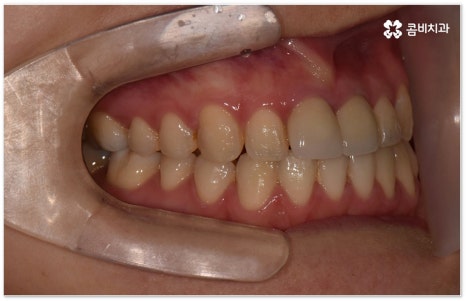

희고 가지런한 치아를 드러내며 환하게 웃는 사람을 보면 자기도 모르게 호감이 가곤하죠, 이처럼 대인 관계에서 치아는 좋은 인상을 만드는 데 심미적으로 큰 역할을 할 뿐 아니라 식사시 음식물을 저작하고 발음을 제대로 하는 데도 많은 도움을 주기 때문에 만약 타고난 치아가 삐뚤어졌거나 위아래 교합이 제대로 맞지 않는다면 이를 기능적 심미적으로 바로잡아 주기 위해서 치아 교정 치료를 고려해 볼 수 있습니다.

이때 성장기 청소년이 아니면 교정 치료를 받을 수 없는지, 교정 치료에 적기가 따로 정해져 있는지 궁금해 하시는 분들이 있는데 관련 기술의 발달로 나이에 크게 구애받지 않고 각자의 상황에 맞게 치료를 진행할 수 있으니 먼저 꼼꼼한 진단 및 상담을 받아보시길 바라고 있어요.

특히 업무적으로나 생활적으로 대인 관계가 활발하신 중장년 성인분들의 경우 치료 기간이 너무 오래 걸리지 않는지, 치아교정장치 가 너무 눈에 띄지는 않는지 궁금해 하시는 경우가 많이 있는데요. 말씀드렸던 것처럼 기술이 발달하면서 다양한 치아교정장치 가 나와있고 치아교정장치 자체는 결과에 크게 영향을 주지 않으므로 몇몇 케이스를 제외하면 환자분들께서 중요하게 생각하는 바 (심미성, 합리성 등) 를 반영할 수 있는 여지가 많이 있기 때문에 숙련된 의료진과 충분히 상담하셔서 각각의 장단점을 잘 살펴보시고 자신에게 꼭 맞는 장치를 고르시면 되니 크게 걱정하실 필요는 없을 거예요.